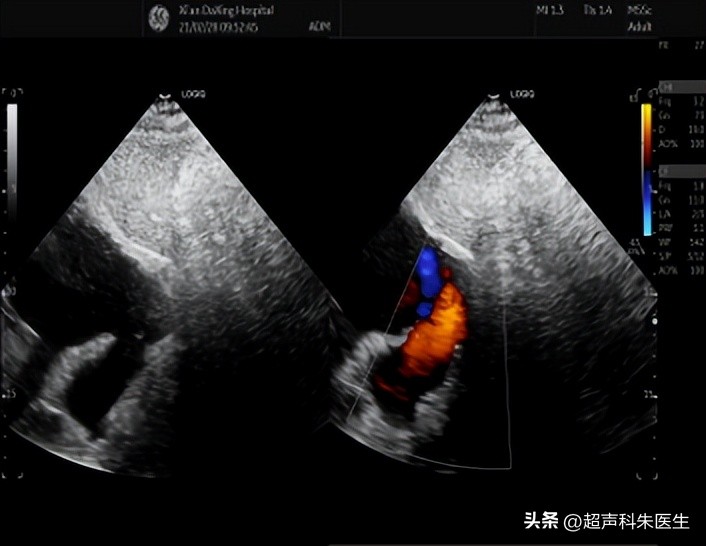

首选 超声 检查,直接征象:房间隔或冠状静脉窦顶盖的回声失落和房水平分流。

2.右室流出道增宽,肺动脉轻度增宽,肺动脉瓣口血流速度增快。